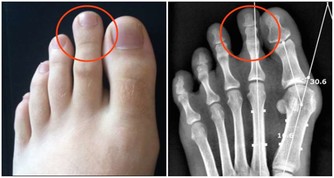

3、痔瘡也是因為缺乏維生素B2引起的。

輕微缺乏維生素B2人體不會有任何感覺,但到一定程度時就會出現明顯的症狀,首先,在人體最薄弱的地方,通常是消化道的首尾兩端,即口腔或肛門的局部,出現充血、腫脹,隨後皮膚或粘膜出現潰瘍,然後開始出血,這即是口腔潰瘍和痔瘡。如果長期缺乏維生素B2,那麼人體其它部位也會出現同樣的症狀。